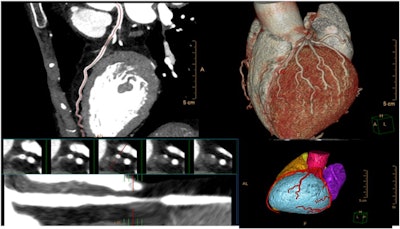

In other news, Philips unveiled the next generation of its Advanced Visualization Workspace. The platform features AI algorithms and workflow support for multiple imaging modalities and specialties, including radiology, cardiology, neurology, and oncology.

More than 70 clinical applications are now available on Advanced Visualization Workspace, including a new cardiac MR suite. Other new features include an upgraded AI-powered CT Alberta Stroke Program Early CT Score (ASPECT) scoring feature that indicates early signs of brain infarction on non-contrast CT exams. Philips has also enhanced its CT Liver Analysis software, which now includes tools for analyzing and quantifying the whole liver, liver segments, and user-defined regions of interest.

Once again, Philips also featured Spectral CT 7500, its flagship CT scanner that's been optimized for routine spectral imaging. The company emphasized the dual-energy scanner's benefits in oncology imaging, cardiac imaging, and interventional radiology. In case studies, the system has yielded 34% faster time to diagnosis, 25% less repeat scans, and 30% fewer follow-up scans, according to the vendor.